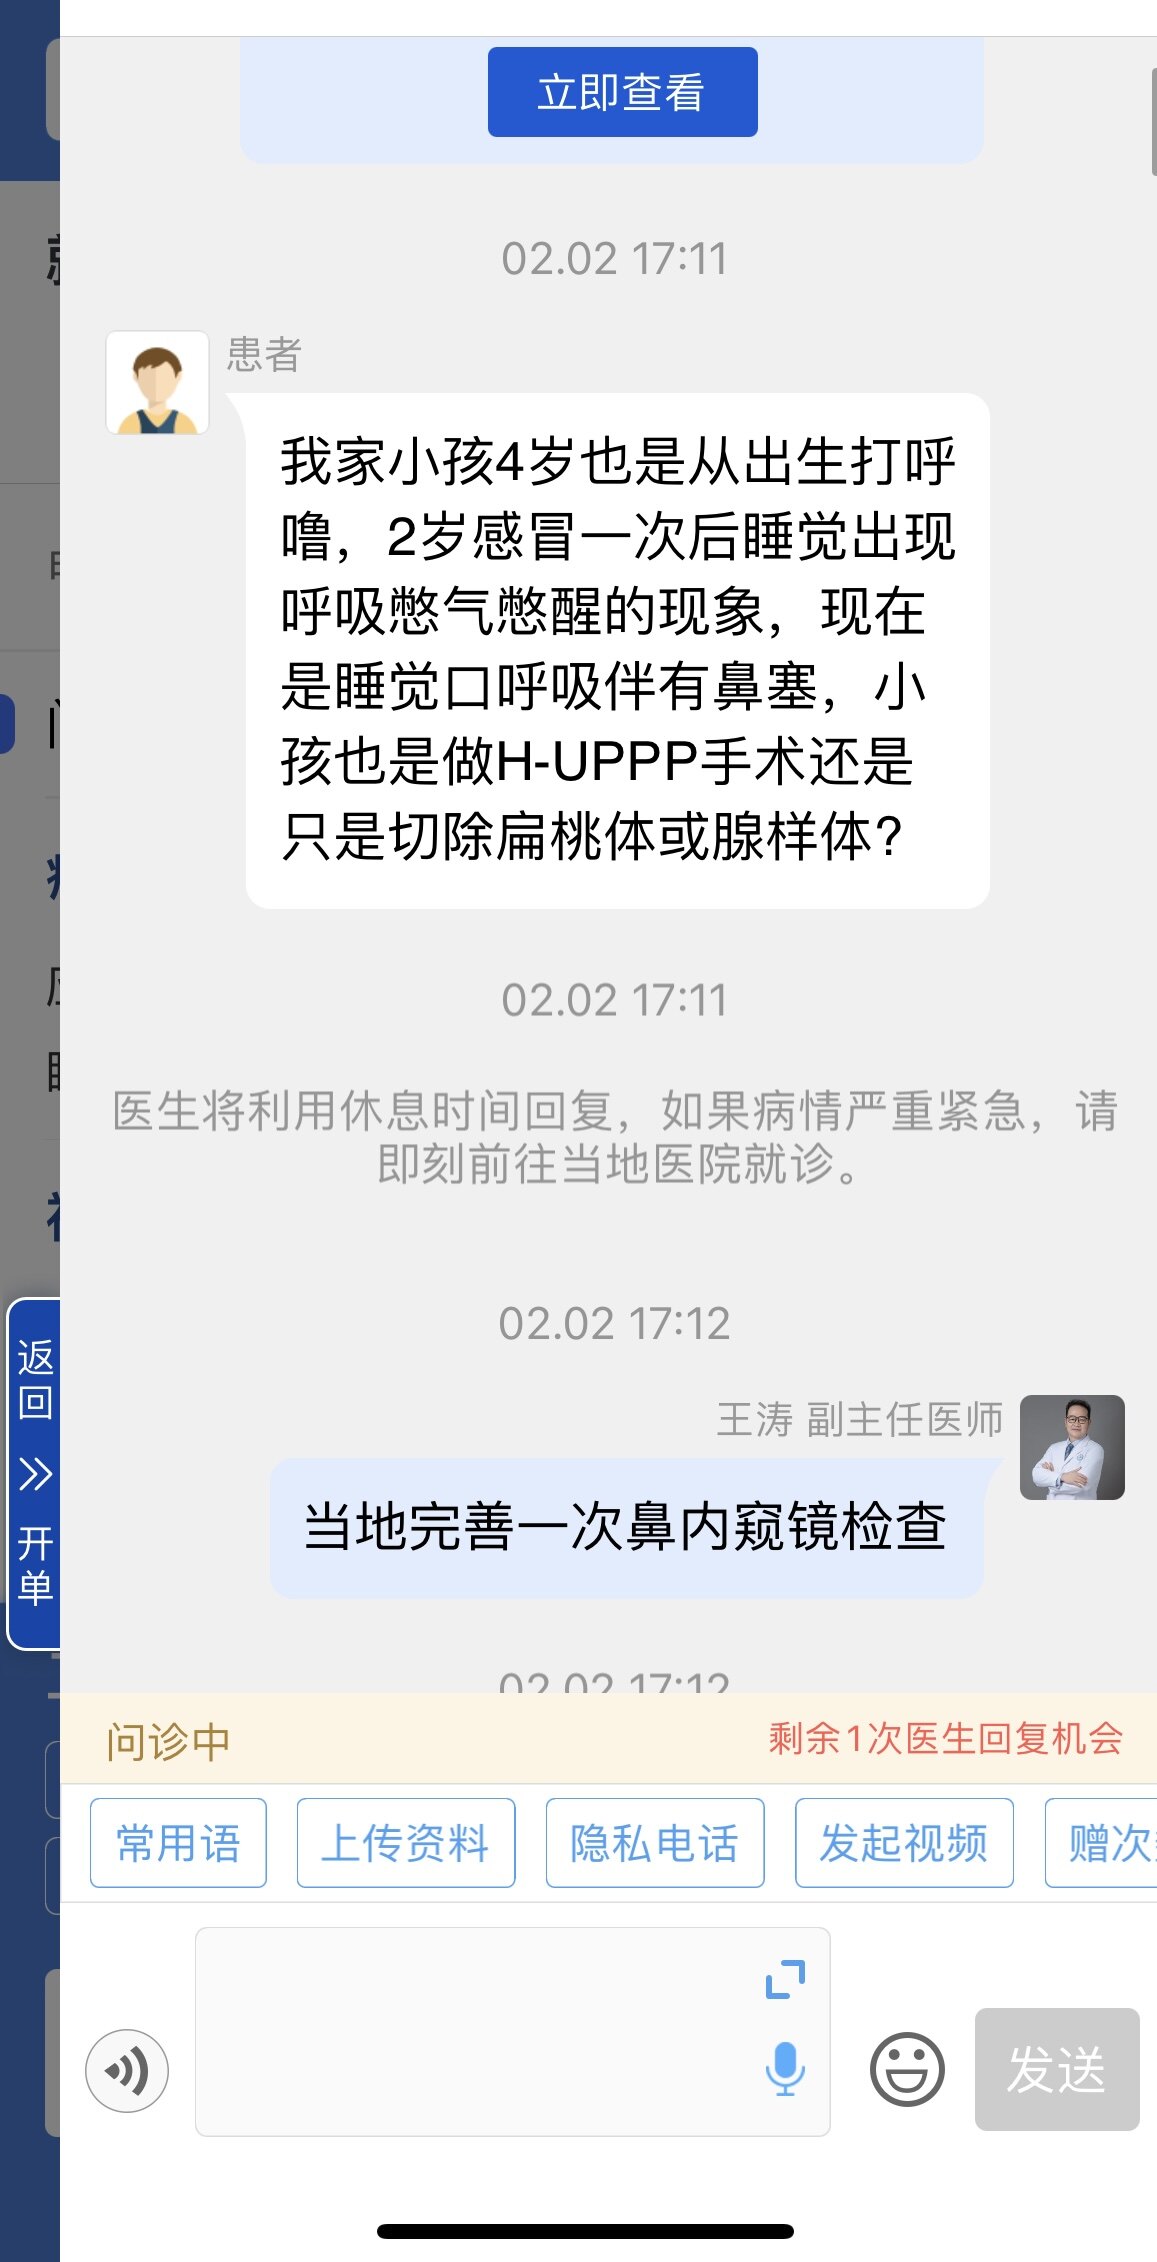

之前同一天做过“鼾症兄弟”、“鼾症兄妹”和“鼾症父女”,这是第一次给“鼾症母女”同一天手术。这对母女来自新疆巴音郭楞,重度鼾症父亲37岁,因为扁桃体肥大,自小打鼾,4年前产后打鼾加重,伴夜间憋醒,严重影响睡眠,当地医生建议患者戴呼吸机,但是她无法耐受呼吸机。电话咨询后,下定决心来广州找我手术。同时她也把4岁女儿打鼾和张口呼吸的情况也详细告诉我,鼾症女儿因为扁桃体3度肥大,腺样体堵塞后鼻孔2/3,造成张口呼吸,对于这样的孩子,一定需要早点手术干预,不然会影响面部发育和生长发育,甚至智力发育。所以我就让她们母女一起来广州找我手术。手术时发现母女俩的扁桃体肥大,因为女孩子4岁,我常规保留双下极扁桃体的1/5和腺样体的1/5。希望母女手术后身体早日恢复正常!有一个安稳的睡眠质量,健健康康的生活!